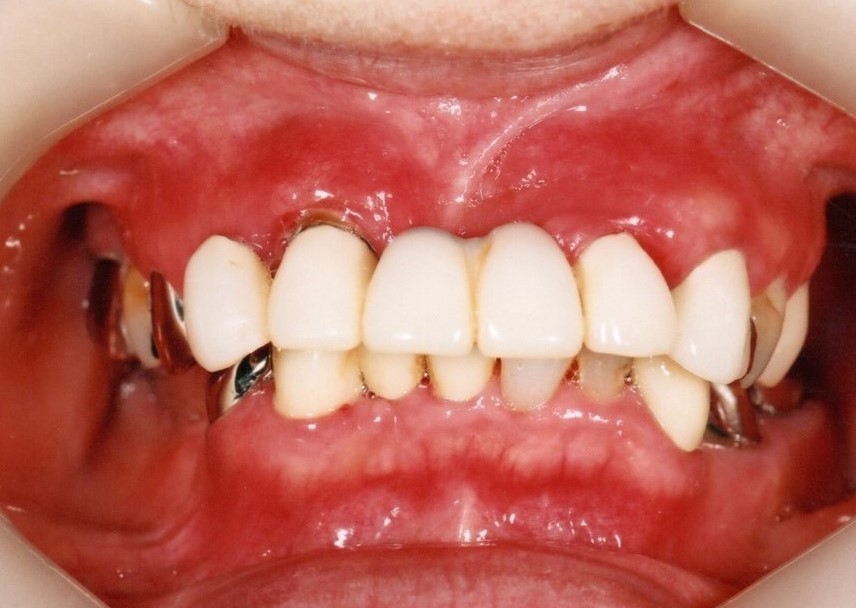

入れ歯

入れ歯装着前

入れ歯は一般的には歯を多く失った時に行う治療法で、型を取って、噛み合わせを記録して製作する取り外し可能な物です。保険で製作できますが、薄くて快適な入れ歯や、バネのないノンクラスプデンチャーは自費治療になります。

入れ歯は粘膜の上に乗せているだけなので噛むと沈み込み、土台の歯にバネの栓抜き効果が加わり、その歯が数年でダメになります。更に骨も経年と共に吸収していくので、合わない入れ歯を使用していると、更に悪化の速度が増します。

入れ歯の欠点

バネを掛けた歯は4年で90%に虫歯ができ、栓抜き効果で次々に歯が抜けてしまいます。最終的に総入れ歯になります。

入れ歯を付けている部分の顎の骨が1年間に0.5~1.0㎜ずつ痩せてしまうのです。だから、入れ歯は合わなくなるのです。